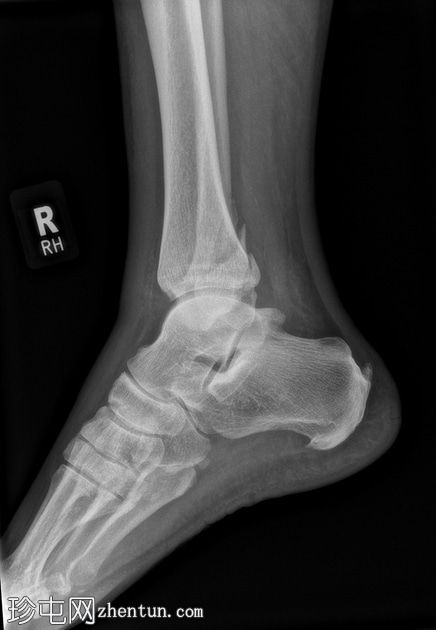

X光片

1.jpg

正面

腓骨下端轻度螺旋形骨折,位于下胫腓联合水平(Weber B),骨折移位,伴有轻度软组织肿胀。

踝关节内侧间隙增宽6毫米(正常值<4毫米),胫腓间隙增宽,胫腓重叠减少,这些表现提示胫腓联合损伤和踝关节不稳定。

踝关节内侧软组织阴影,提示内侧副韧带损伤。

后踝(踝骨)骨折轻微移位。

可见腓籽骨。

足底跟骨骨刺。

可见跟腱末端钙化性病灶。